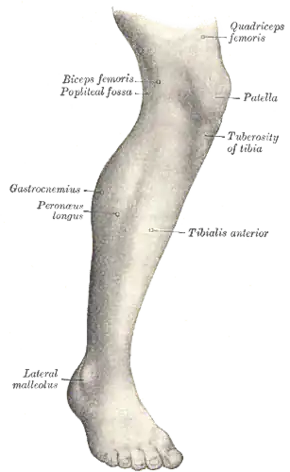

Lateral aspect of right leg. (Tuberosity of tibia labeled at center right.) | |

The tuberosity of the tibia, tibial tuberosity or tibial tubercle is an elevation on the proximal, anterior aspect of the tibia, just below where the anterior surfaces of the lateral and medial tibial condyles end.